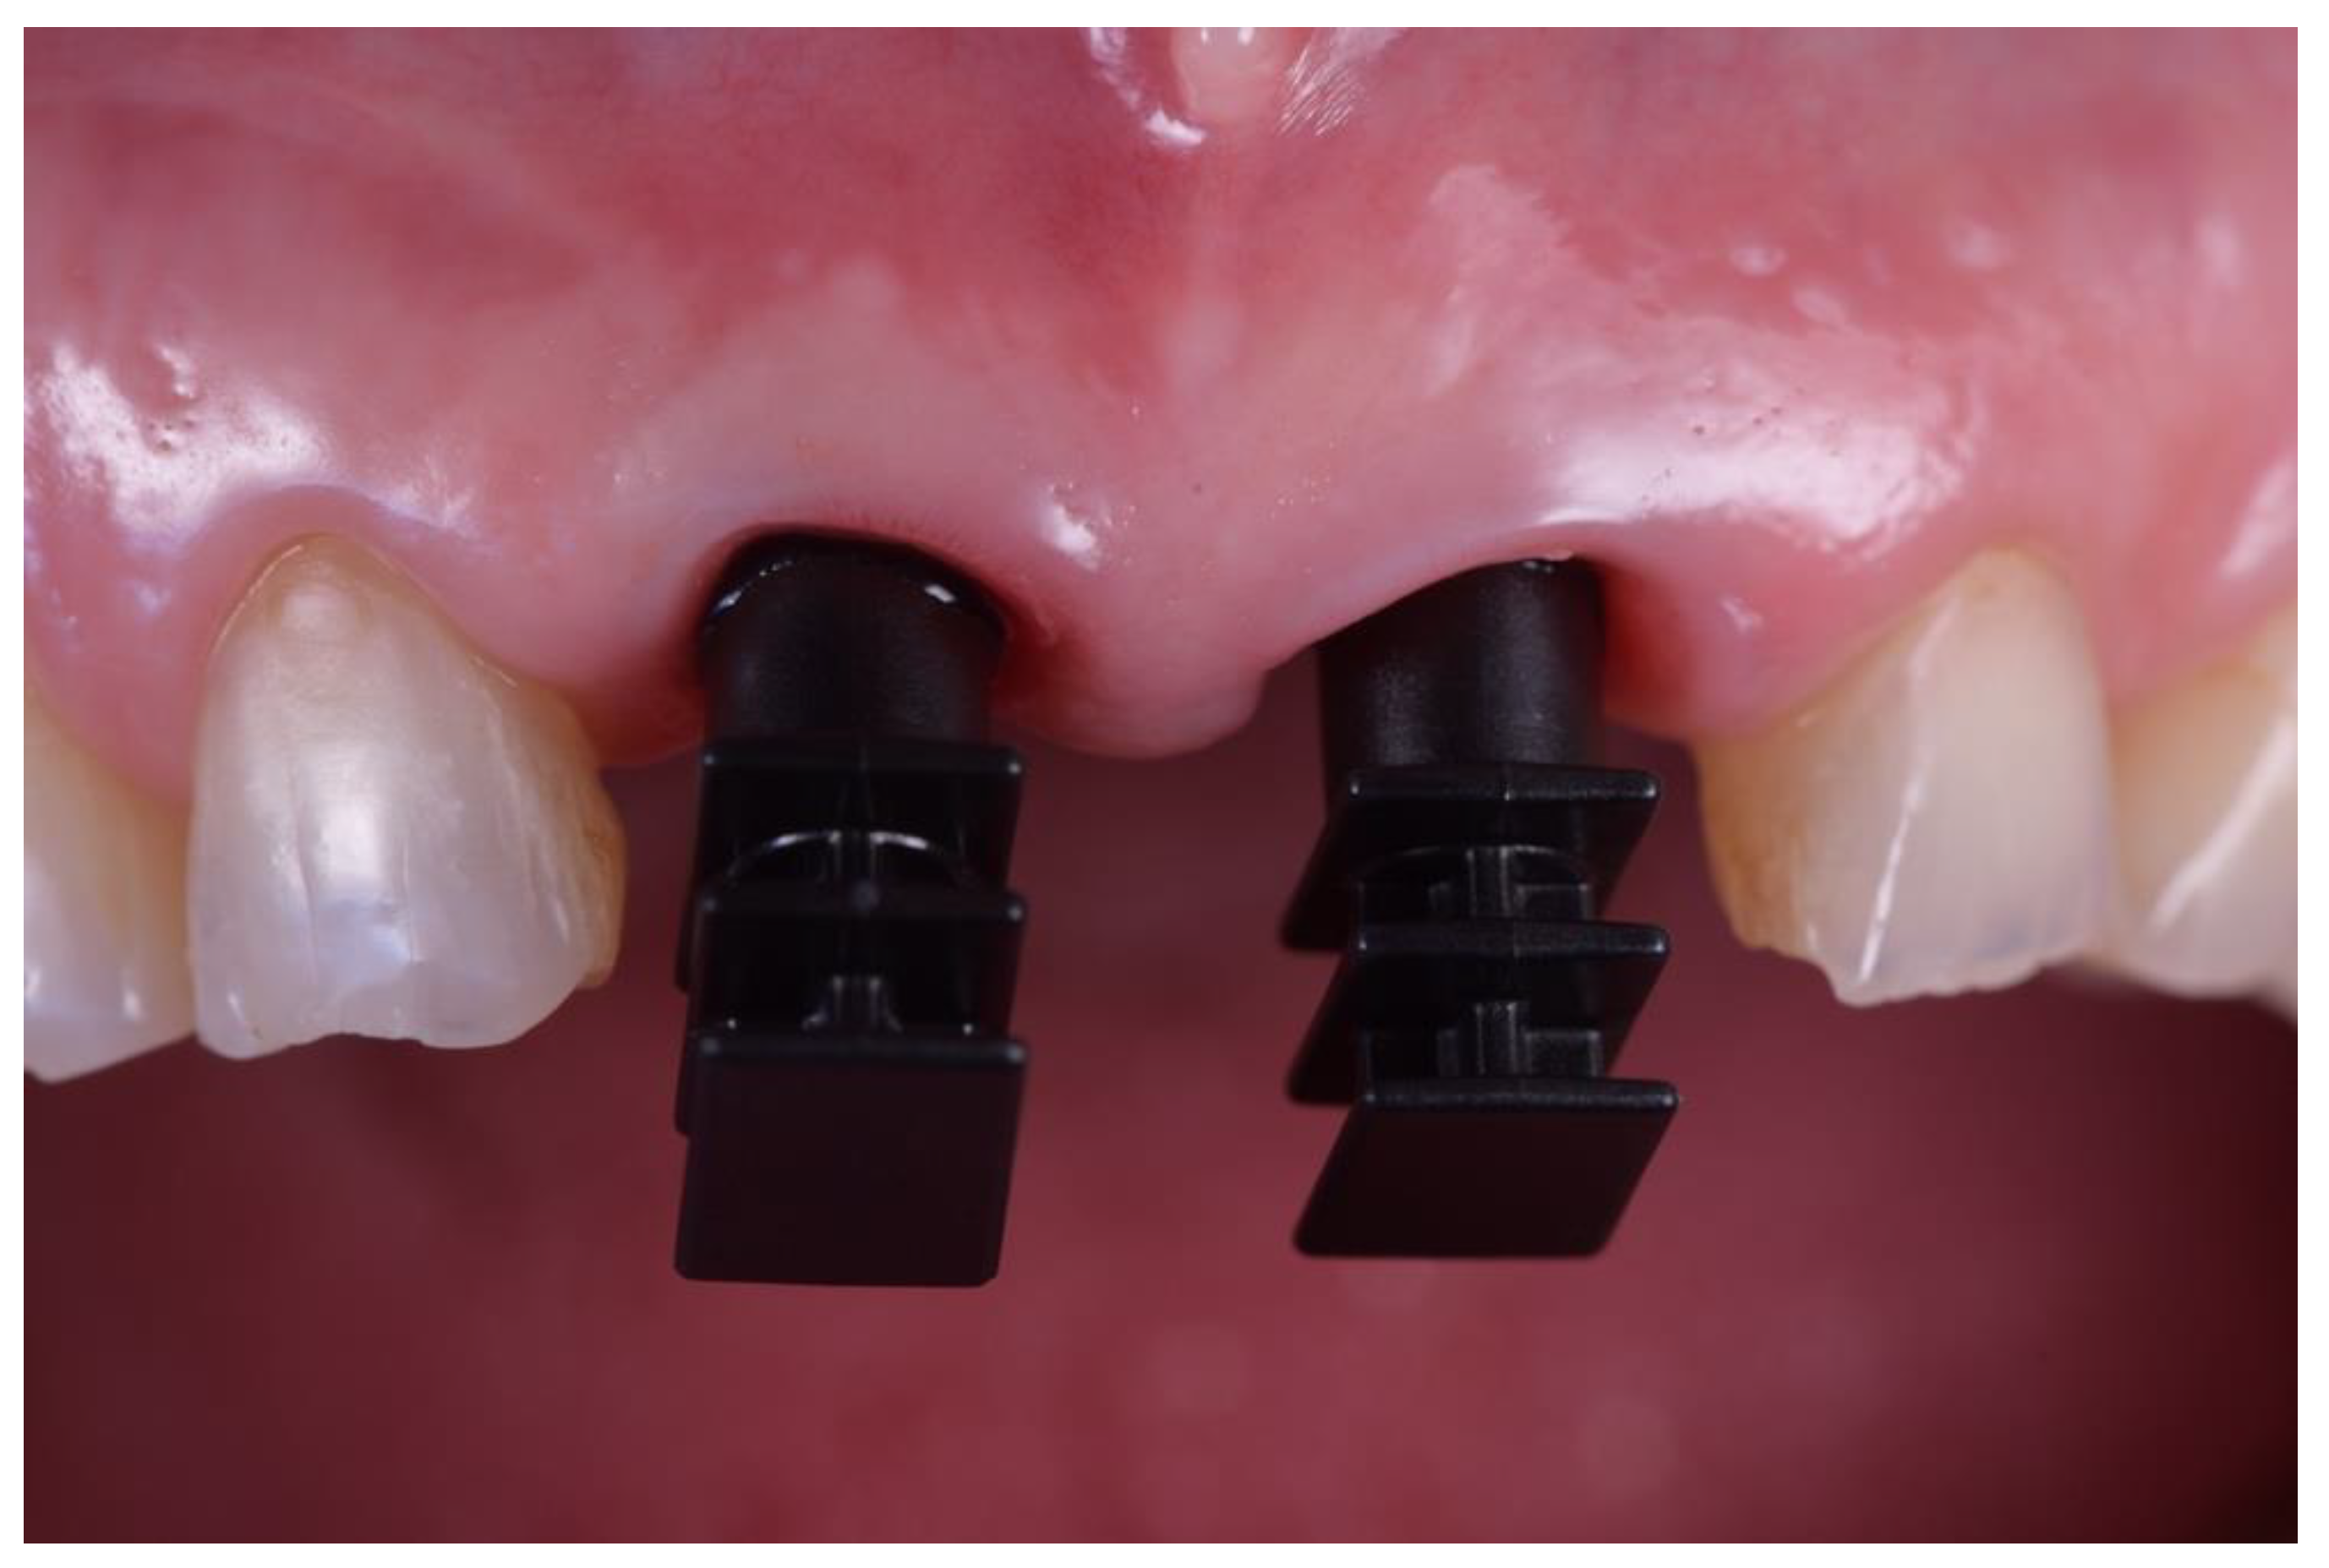

2. Materials and Methods

Implant Characteristics

3. Results